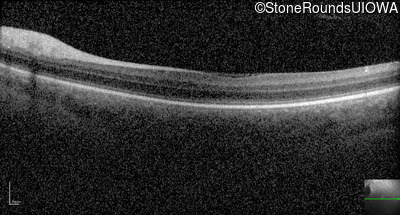

Optical Coherence Tomography - Right - 10/200

Exemplar / OCT Stack

Optical Coherence Tomography - Left - 10/100